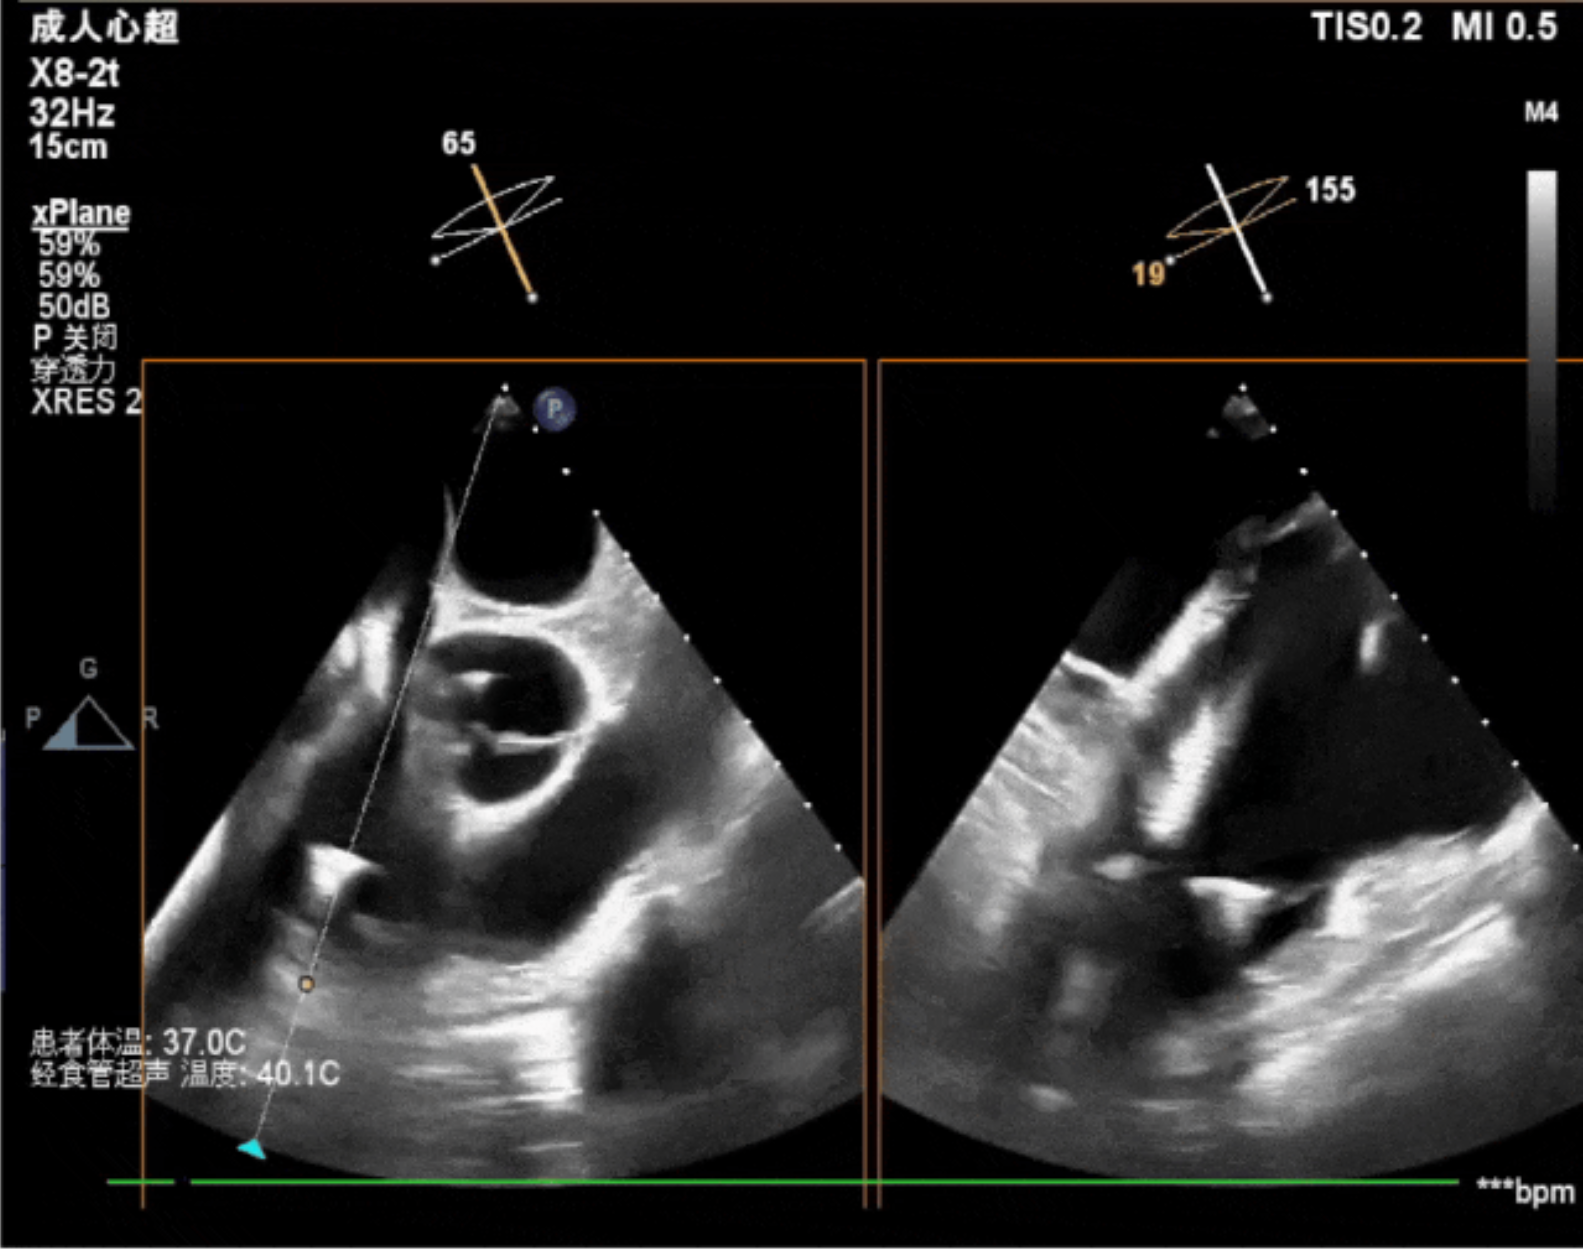

術(shù)中影像

術(shù)前DSA造影可見(jiàn)三尖瓣大量返流呈瀑布樣,右室偏間隔側(cè)可見(jiàn)無(wú)導(dǎo)線(xiàn)起搏器一枚。

術(shù)中經(jīng)食道超聲輔助下可見(jiàn)LuX-Valve Plus夾持件抓捕瓣葉狀態(tài)良好,夾持件在位,室間隔錨定位置良好,假體瓣膜整體錨定狀態(tài)穩(wěn)固。

術(shù)后即刻經(jīng)食道超聲可見(jiàn),三尖瓣假體瓣膜位置合適,牛心包瓣葉運(yùn)動(dòng)狀態(tài)良好,開(kāi)閉正常,瓣周及瓣葉對(duì)合緣處未見(jiàn)明顯返流,心電圖及心包狀態(tài)較術(shù)前無(wú)明顯變化。

本次直播手術(shù)中,手術(shù)團(tuán)隊(duì)在超聲與DSA等多維影像手段的支持下,精準(zhǔn)嫻熟的完成LuX-Valve Plus瓣膜的植入,器械操作時(shí)間僅為30分鐘,瓣膜植入后術(shù)中即刻三尖瓣返流消失,多普勒超聲下無(wú)明顯瓣周漏或中心性返流,肺動(dòng)脈壓正常,平均跨瓣壓差僅為1mmHg,人工瓣膜運(yùn)動(dòng)正常,術(shù)后1小時(shí)內(nèi)該患者即安返病房。